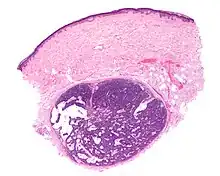

| Micrograph of a spiradenoma (bottom-center of image). H&E stain. | |

As determined by the microscopic histopathological appearances of their hematoxylin and eosin-stained samples, spiradenomas are non-encapsulated nodular skin lesions that extend into the dermis. The lesions consist of a relatively disorganized and dense array of proliferating basophilic cells (i.e. cells appearing blue because of their abnormally large uptake of the hematoxylin stain).[9] These cells are arranged as small cells with hyperchromatic nuclei and scant cytoplasm layered outside and larger cells with vesicular (i.e. vesicle-containing) nuclei layered inside of intertwining strips.[16] Lymphocytes commonly populate these lesions. Some lesions may merge the histopathological features of spiroadenomas with those of cylindromas.[9] Cylindromas are hair follicle tumors that consist of basal cells (i.e. small, round cells similar to those seen in the lowest layer of the skin's epidermis) which are arranged in ("jigsaw-like"[17] cylindrical patterns separated by thickened basement membranes. The cylindroma tissues may also contain disorganized, dense arrays of proliferating basophilic cells.[9]